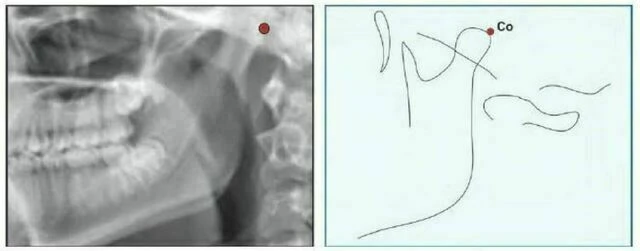

Condylion (Co) là điểm sau nhất và trên nhất ở lồi cầu xương hàm dưới.